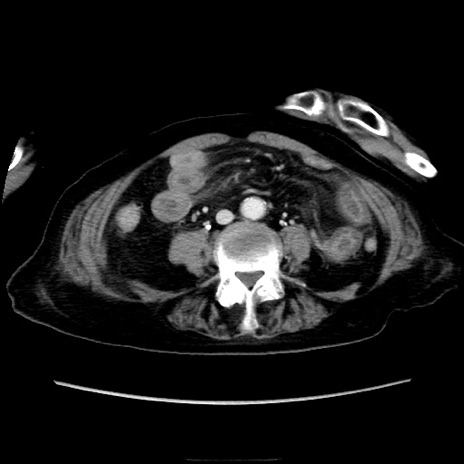

症例40(横断像)

【症例】90歳代女性

【主訴】腹痛・嘔吐

【現病歴】 食欲低下、嘔吐があり昨日他院受診。肺炎と診断され入院となる。入院後より腹部全体に圧痛あり。胃管留置され経過みていたが、症状持続するため、

当院転院となる。

【既往歴】胸椎圧迫骨折、胆石症

【身体所見】腹部:中央に激痛あり、圧痛あり、反跳痛不明

【データ】WBC 17100、CRP 18.82

横断像